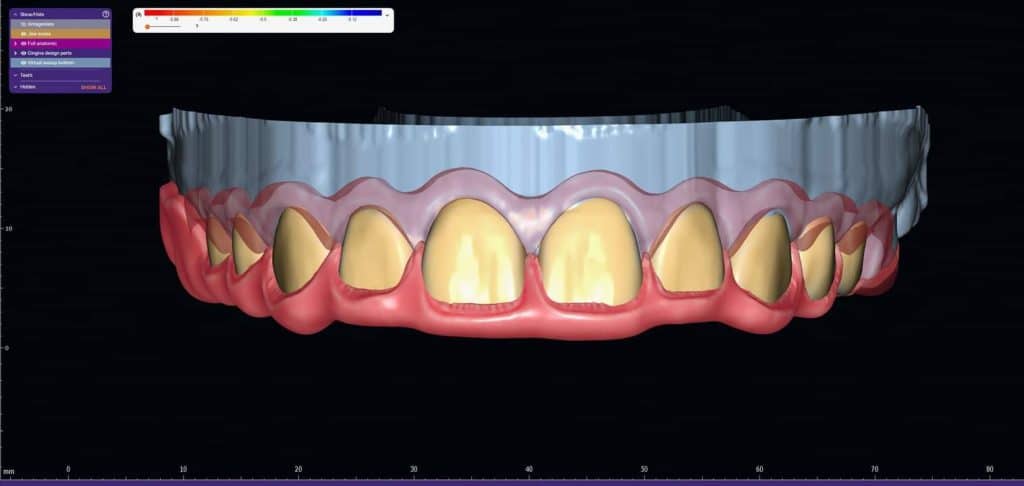

The case presented in this case report is for a 27-years-old female patient with a chief complaint of aesthetic correction for her smile. The patient was unhappy with her smile. After clinical examination, there were previous old composite veneering done poorly and incorrectly to close the multiple interdental spacing. After discussing the various treatment options (i.e., orthodontic treatment, direct, or indirect veneers), indirect ceramic veneering was selected. The step-by-step treatment protocol is presented in the images below.

Special thanks to my friend, Dr. Ali Al-Qrimli the CEO of Digital IDEA dental lab for fabrication of the ceramic veneers and the digital designing, with many thanks for the dental ceramist, Dt. Ali Kadum who did the ceramic build-up for this case.